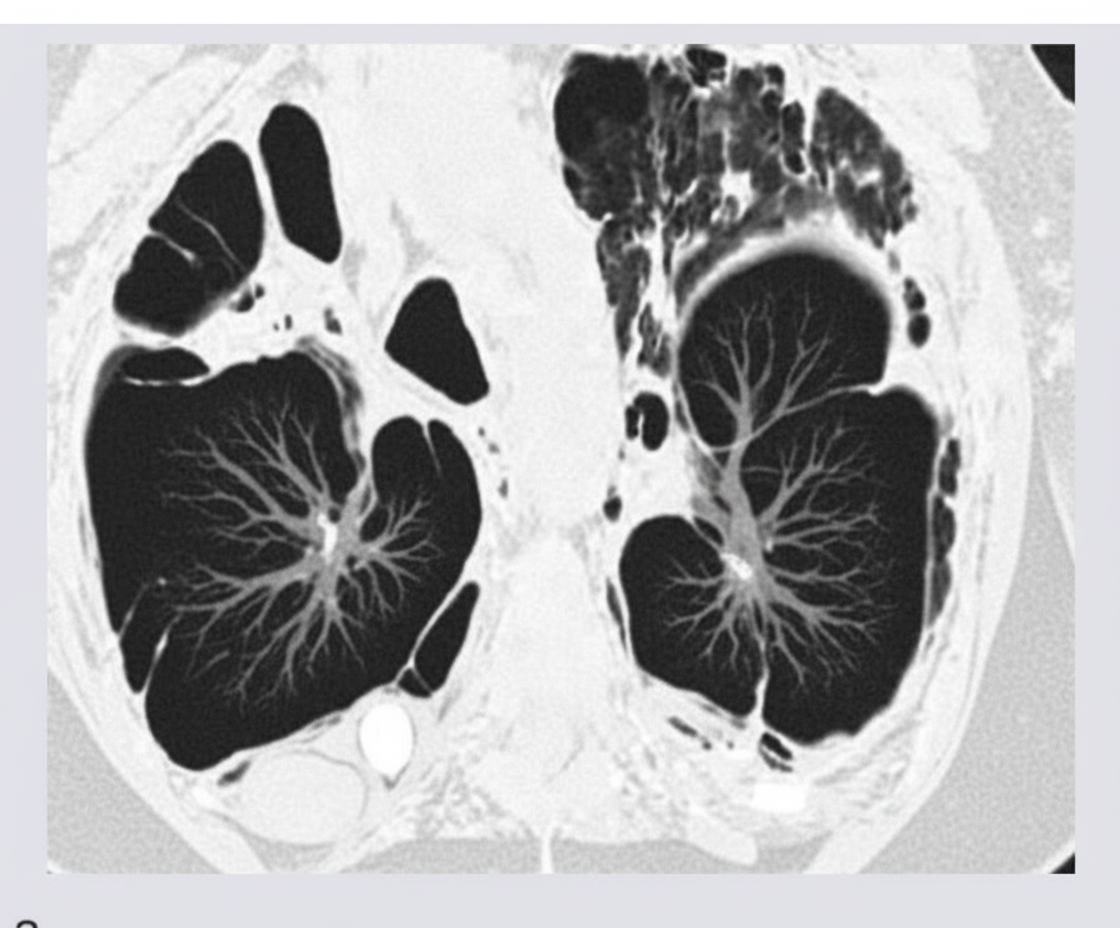

The following CT chest shows the presence of?

Explanation: ***Emphysema*** - CT chest shows characteristic **low-attenuation areas** (hypodense regions) and **bullae** formation with **vascular rarefaction** in lung parenchyma. - **Hyperinflation** with increased anteroposterior diameter and flattened diaphragm are typical CT findings of emphysema. *Artifact* - CT artifacts appear as **streak lines**, **motion blur**, or **beam hardening** effects that don't represent actual pathology. - Would not show the **parenchymal destruction** and **air trapping** pattern characteristic of emphysema. *Silicosis* - CT typically shows **upper lobe nodules** with **eggshell calcification** of hilar lymph nodes from silica dust exposure. - Presents with **progressive massive fibrosis** rather than the **low-attenuation areas** seen in emphysema. *Pneumonoultramicroscopicsilicovolcanoconiosis* - This is essentially a **fancy term for silicosis-like disease** caused by volcanic ash and fine silica particles. - Would show **fibrotic changes** and **nodular patterns** similar to silicosis, not the **hyperinflated** appearance of emphysema.